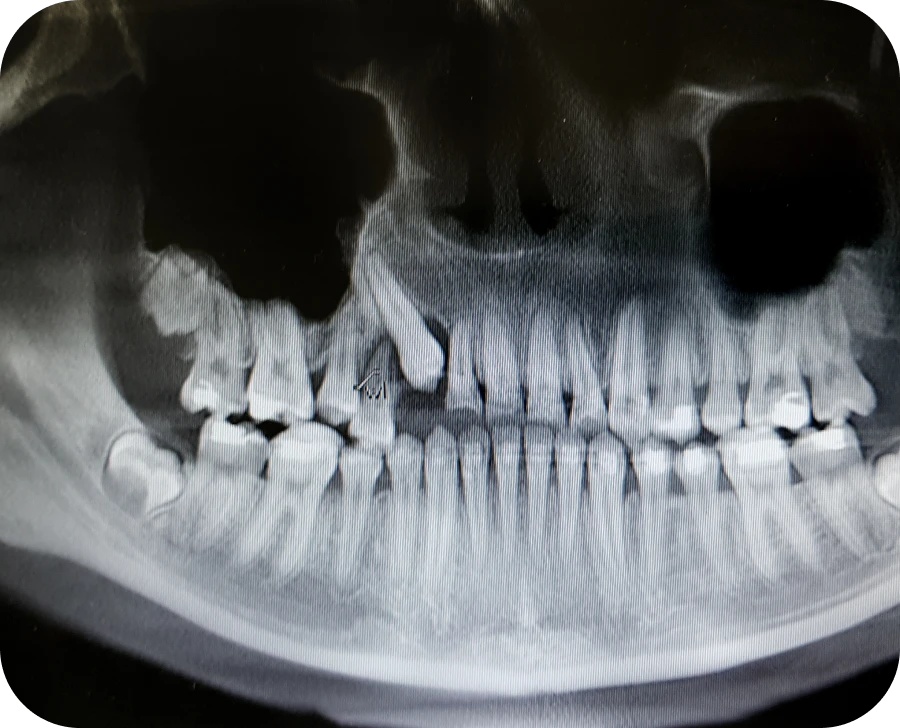

Face à une suspicion de dent incluse, il est important d’agir rapidement. Une première étape consiste à réaliser une radiographie panoramique afin de visualiser l’ensemble de la dentition, y compris les dents encore enfouies. Cette image permet d’évaluer précisément la position, l’orientation et l’état des racines. Une fois ce bilan établi, un échange avec un orthodontiste permet d’envisager les options thérapeutiques adaptées à la situation. Dans certains cas, lorsque la dent est encore immature, une simple surveillance peut suffire. Toutefois, si le blocage persiste, une intervention devient nécessaire.